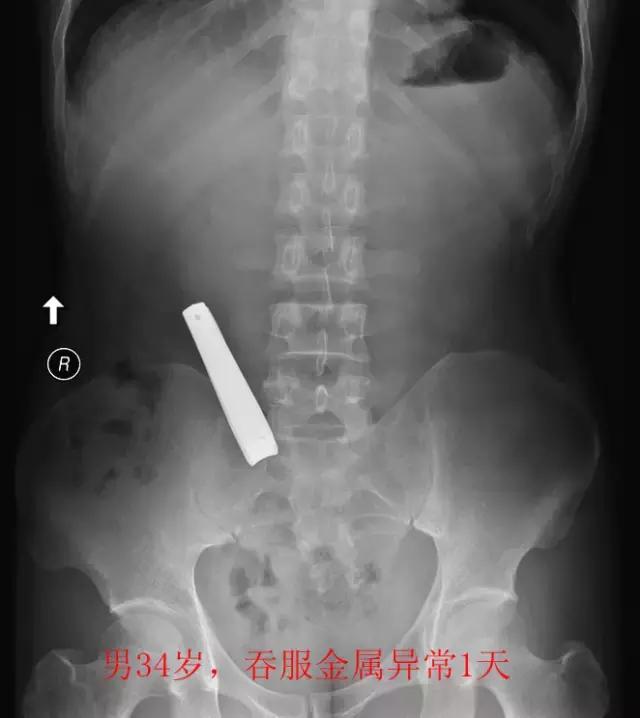

最后,是“看图识物”环节,请大家辨认下面三张图中的物体,欢迎在留言区发表你的看法哦。